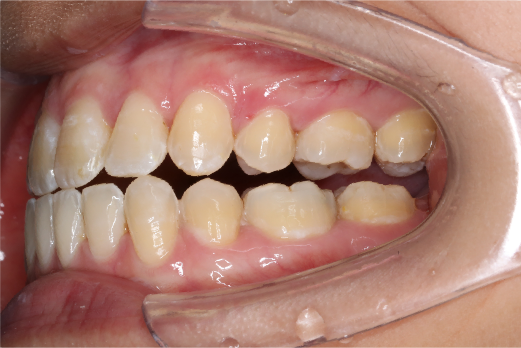

2018.11.14  术后磨牙尖牙I类关系,中线齐,覆合,覆盖正常

宏观评价:面部对称,面下三分一比例协调,上下唇凸度正常,上颌牙列内收转矩控制良好,下颌后缩改善,颏唇沟变得更加柔和,术后达到基本直面型。

迷你观评价:上下牙齿中线与面中线对齐,笑弧协调,微笑时牙龈暴露量正常,微笑时横向正常,左右唇基本对称。

微观评价:牙齿整齐,咬合关系良好,上下前牙转矩及突度控制良好,磨牙关系I类,尖窝咬合关系良好,OB,OJ正常。